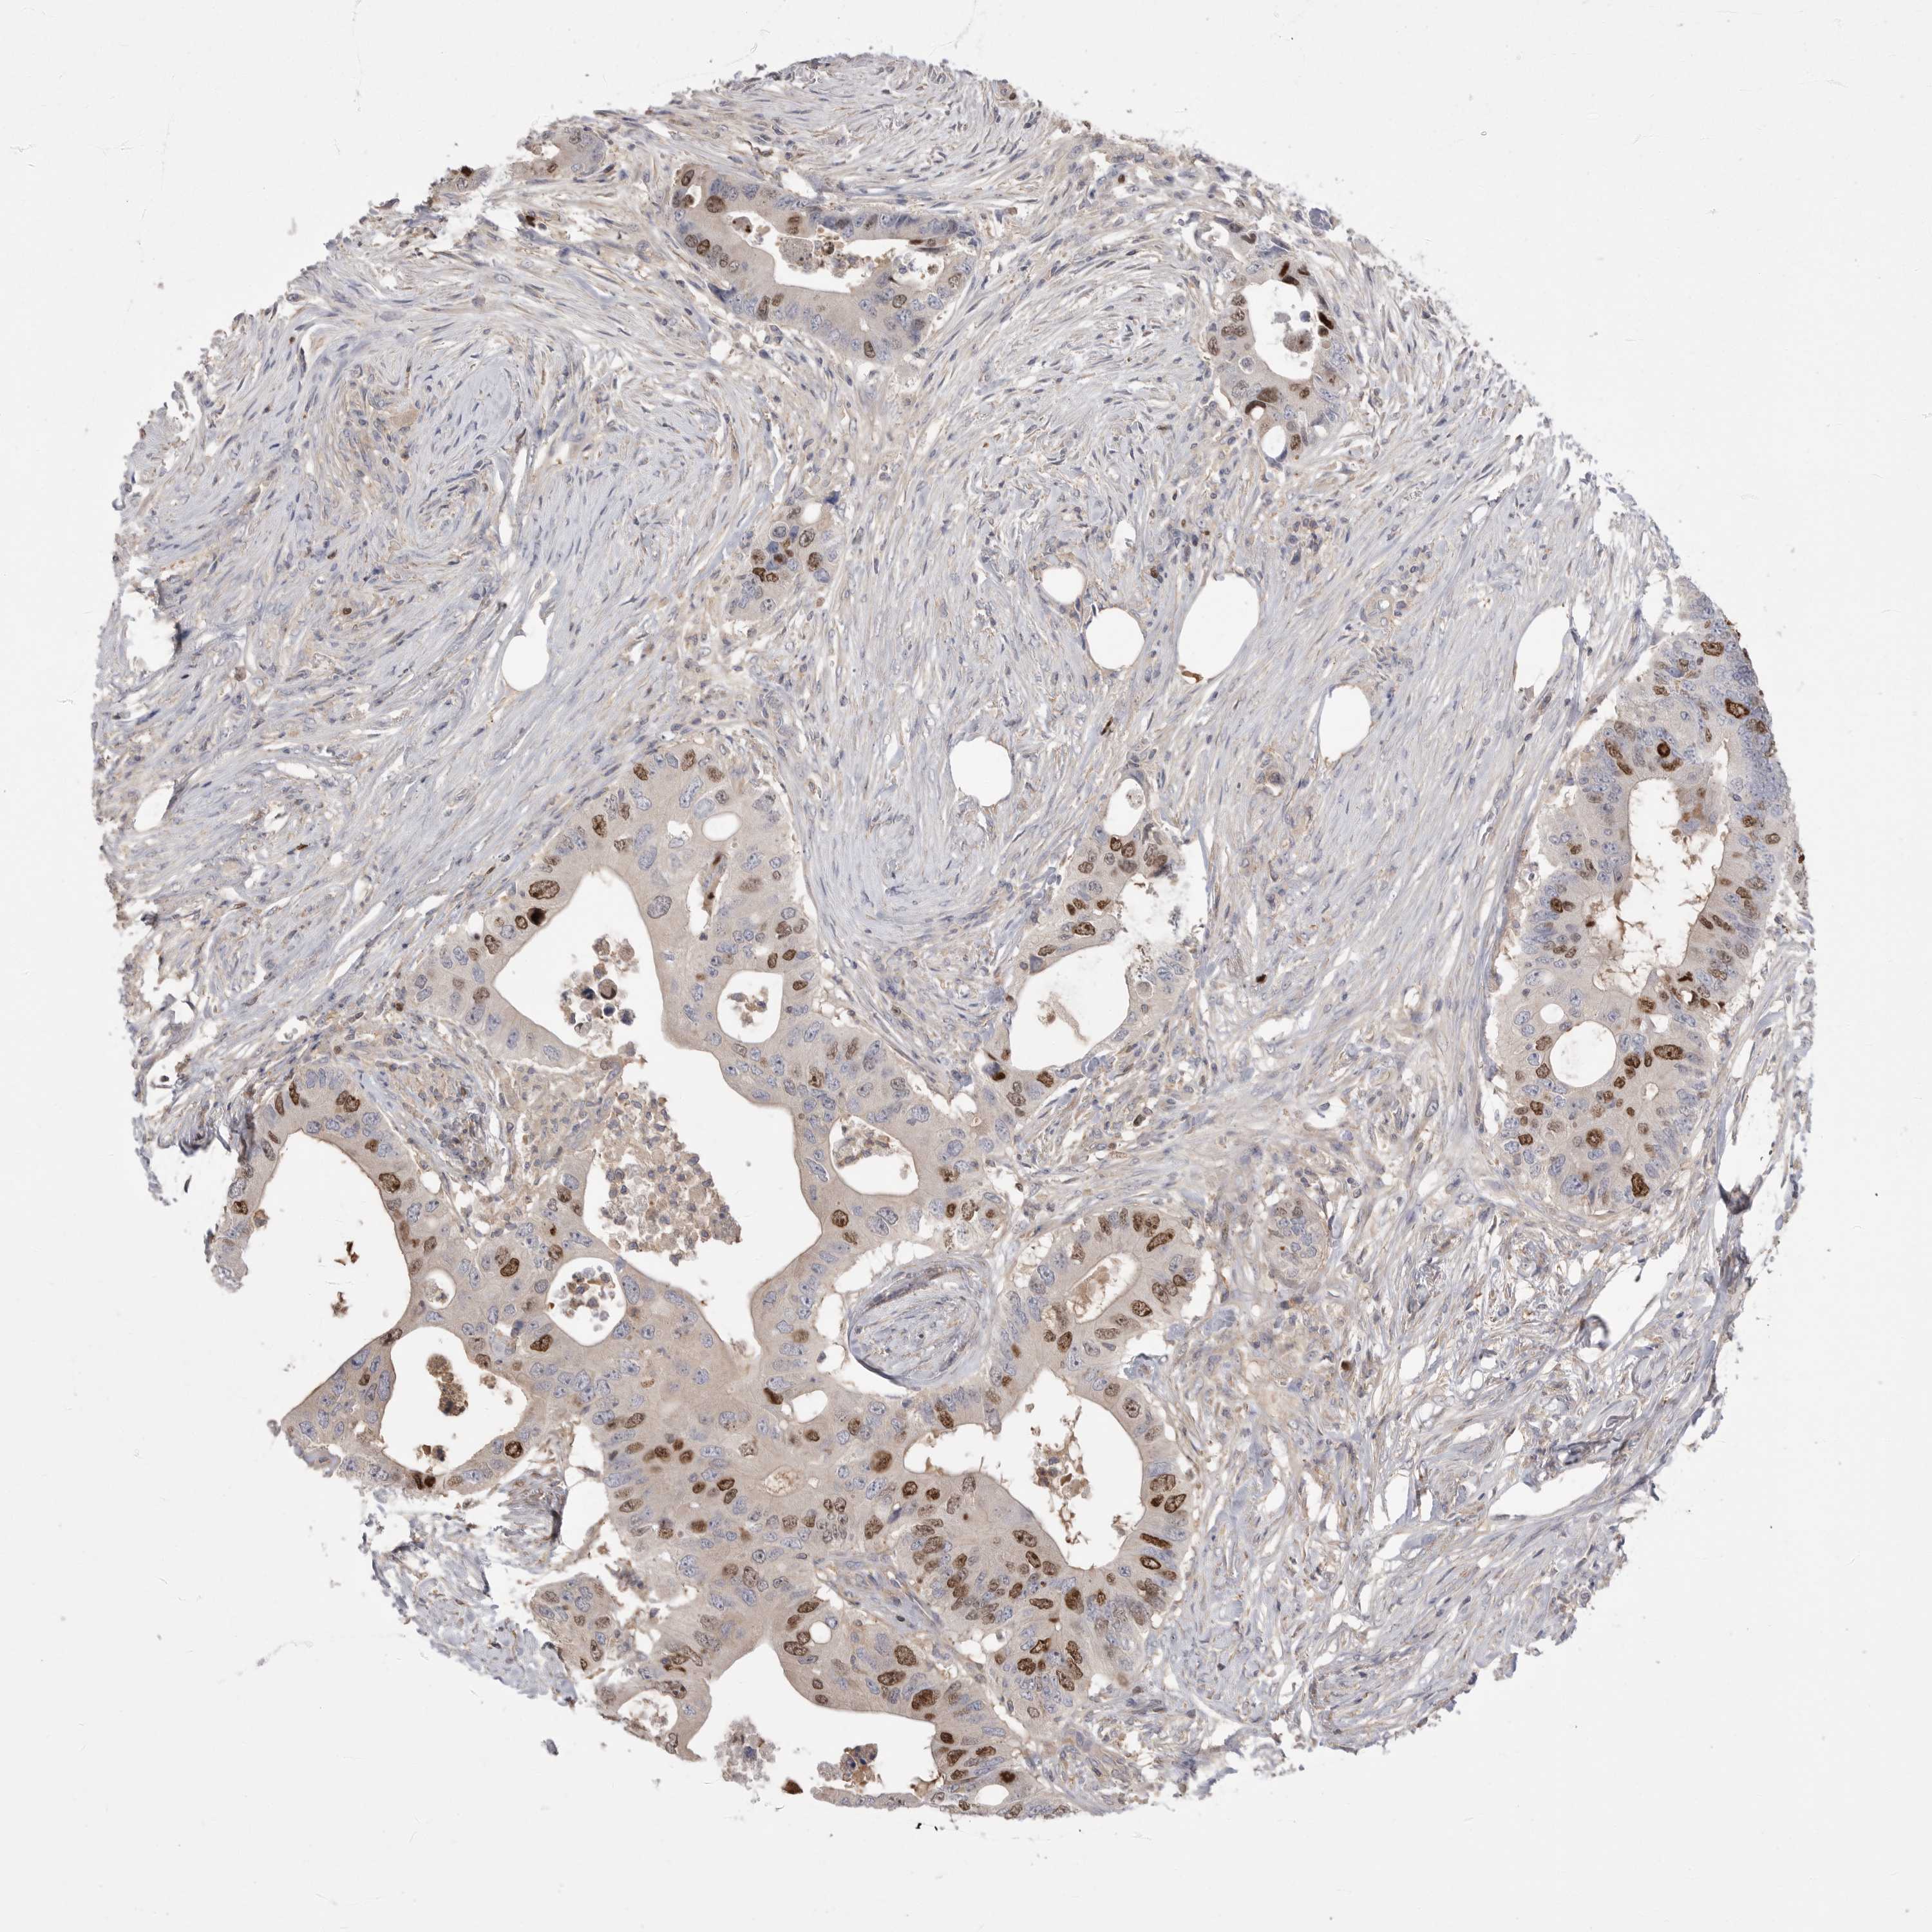

CANCER COLORECTAL CANCER Show tissue menu

ANTIBODIES

AND

VALIDATION